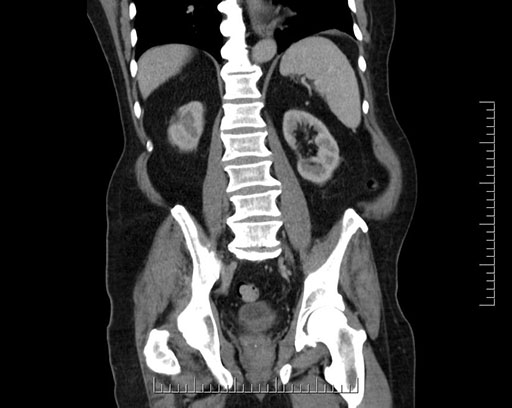

Imaging Analysis

Look through the patient's CT scan to identify any areas of concern for the necessary procedure.

Based on your CT findings, which issue(s) would give reason for "planned slowing down moment(s)" in this case?

Considering a standard Whipple procedure, what step(s) of the operation would you do differently in this case?